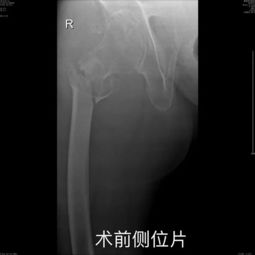

近日,Reddit论坛上一则求助帖引起了广大玩家的关注。发帖者因手指骨折,整个左手都打了石膏,于是向社区寻求推荐只需鼠标就能玩的优秀游戏。附带的X光照片更是让人感同身受。